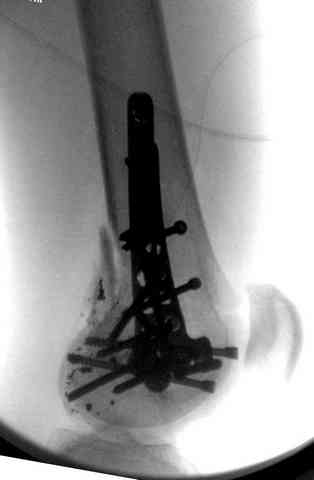

Для фиксации огнестрельных переломов бедра и длинных костей предпочтение отдаем интрамедуллярному методу фиксации, о котором еще в 1993 году написали Bergman M. Tornetta P. Kerina M. Sandhu H. Simon G. Deysine G. Journal of Trauma. [JC:kaf] 34(6):783-5

Но иногда, когда перелом расположен удобно в ране и нет необходимости обнажения кости дополнительным скелетированием, тогда первичную фиксацию можно проводить пластиной с проведением мероприятий по закрытию мягкотканых дефектов.

При отсутствии интрамедуллярной техники, которая относится к load sharing концепции можно заменить фиксацию пластинами. Load bearing, особенно кондилярные пластины, довольно солидная конструкция и такая пластина может выдержать необходимую для бедра нагрузку.

Можно уложить пластину на протяжении всего бедра с применением мини хирургических доступов, только надо согнуть пластину по контуру бедра предварительно.

Bridging technique использовал наш коллега Багавуддин из Йемена, он для фиксации переломов с огнестрельними ранами бедра применял более жесткую пластину LISS. Наличие худощавых больных упрощало работу, и позволяло выходить с достоинством из вынужденного положения при лимитированных экономических условиях.

Если нет ЭОП, тогда для упрощения операции нужно обработать стерильно обе конечности. После укладки пластины через дистальный латеральный доступ проводится фиксация одним шурупом для удержания пластины против кости и через подвертельный доступ остается уложить пластину точно в середину бедра. Любой костный держатель удержит пластину, поможет проверить ротацию и длину конечности сравнительно с другой стерильной стороной, и остается рутинная фиксация двумя или тремя шурупами в сегменте после исправления деформации.

Здесь представлены несколько случаев лечения огнестрельного перелома

3 сегментарный перелом бедра с переломом Хоффа фрагментом, сделано из минимального доступа